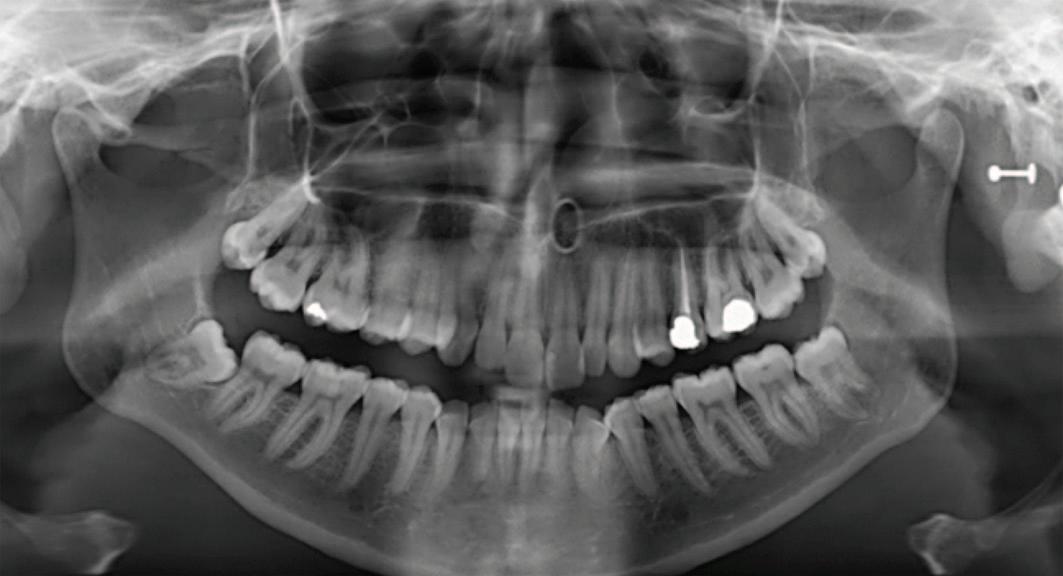

This paper describes a case of intermittent inferior alveolar nerve (IAN) paraesthesia temporally related to episodes of pericoronitis affecting a mandibular third molar in close association with the IAN. A 23-year-old female patient was referred to oral surgery by oral medicine with a two-month history of intermittent alternating numbness and pain associated with the lower left lip and chin. Clinical and radiographic investigations confirmed a partially erupted left mandibular third molar in close association with the IAN. Subsequent conebeam computed tomography (CBCT) revealed that the lower left 8 (LL8) had two mesial and two distal roots. The IAN pathway grooved the distal roots and perforated the mesial. A coronectomy was completed, resulting in the resolution of symptoms.

Given the temporal association between the history of paraesthesia, episodes of pericoronitis and the clinical findings, it was agreed that there was a likely causative association between the pericoronitis and the intimate relationship of LL8 with the IAN. Complete removal of the LL8 was deemed high risk for iatrogenic IAN damage. To reduce this risk, the patient was consented for a coronectomy. The coronectomy was undertaken with a short general anaesthetic without complication, and at the two-month postoperative review, the patient had complete resolution of symptoms and no postoperative sensory deficit. The orthopantomogram taken at this review shows no evidence of periapical infection and the distal retained root is satisfactorily subcrestal (Figure 4). It is acknowledged that following the coronectomy, the mesial root is not at the optimum subcrestal level and has a small radiodense area, which may be residual enamel. This necessitates close follow-up.

FIGURE 4: Postoperative radiograph at two months.

investigation revealed unusual superior migration of the IAN canal as well as the retained roots. Longer-term follow-up is planned to thoroughly evaluate this case.